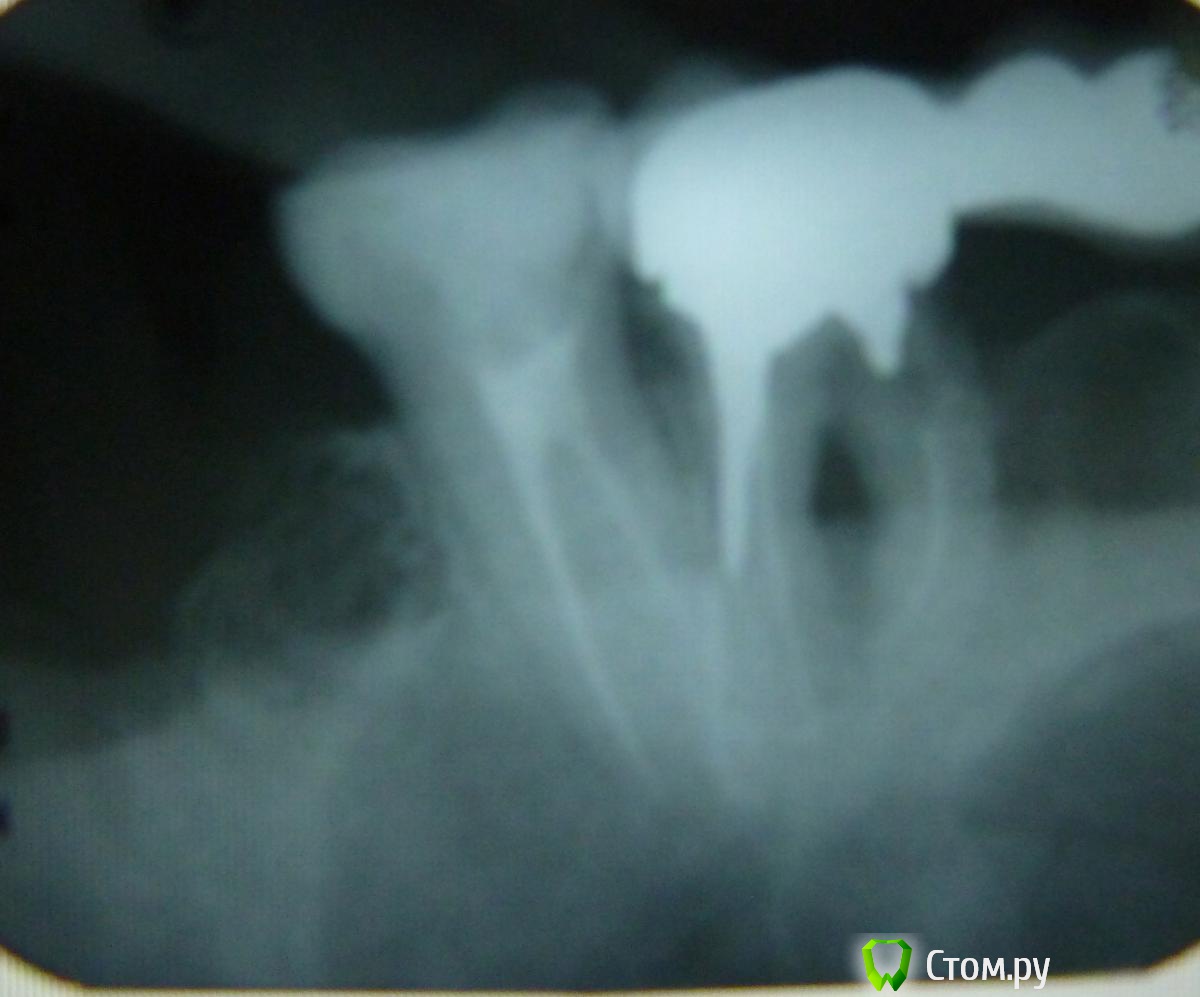

Робинзон Опубликовано 7 июня, 2014 Автор Поделиться Опубликовано 7 июня, 2014 похоже на кореньза 7 -ой еще зубы были?Вот старый снимок до удаления 7-ки, как раз 8-ка хорошо видна. Ссылка на комментарий

Робинзон Опубликовано 7 июня, 2014 Автор Поделиться Опубликовано 7 июня, 2014 похоже на кореньза 7 -ой еще зубы были?За 7-ой еще 8-ка. Ссылка на комментарий